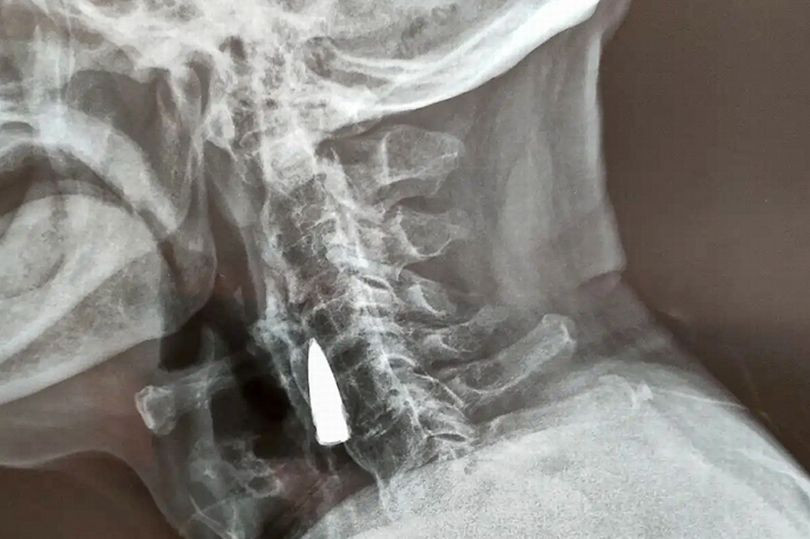

| Bức ảnh chụp X-quang cho thấy viên đạn găm trong cổ của cựu chiến binh suốt 77 năm. Ảnh: ViralPress. |

Thật kỳ diệu, các chuyên gia y tế cho biết viên đạn trong cổ không gây ra bất kỳ vấn đề gì cho Zhao mặc dù nó đã bị găm vào cơ thể ông suốt 77 năm.

Do tuổi cao và viên đạn không ảnh hưởng tới sức khoẻ nên các bác sĩ quyết định không gắp dị vật ra bởi việc lấy nó ra sẽ phải trải qua một cuộc phẫu thuật đầy rủi ro.